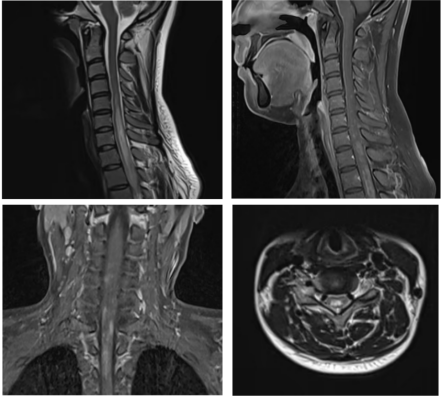

病例一  小崔是一个身强力壮的大四学生,即将离开校园步入社会,一天早上起床感觉头晕,伴有恶心和呕吐,自觉四肢麻木,看东西出现双影,第二天出现走路不稳,在家人的陪同下去了当地县医院,诊断“前庭神经炎”,输液治疗,症状没有明显好转。小崔的母亲非常着急,带着小崔来到沧州市中心医院神经免疫、中枢神经系统感染二科就诊,刘洁琼主任团队通过详细地询问病史、查体,对患者进行了腰椎穿刺显示寡克隆区带(+),头颈胸部增强核磁共振显示大脑和脑干多发异常信号,再次追问病史,小崔入院前4月余曾有右侧肢体麻木,未予重视,自行好转,判断小崔所患的疾病是复发缓解型多发性硬化,立即给予患者激素冲击治疗,数天后小崔症状完全缓解。为了防止疾病再次复发对小崔日后的生活和工作造成影响,刘洁琼主任结合国际最新研究成果及指南,给予患者生物制剂皮下注射,患者目前无不良反应,已经进入工作岗位开始了新生活。   病例二 张女士两年前生孩子后出现右眼视物模糊,就诊于当地医院诊断为视神经炎,一直服用免疫抑制剂治疗。半月前的一天张女士感觉背部发麻,以为着凉,未予重视,后来张女士又出现了双下肢麻木无力、走路不稳,同时自觉排尿、排便费力,张女士的家人马上意识到了问题的严重性,赶紧带着张女士就诊于沧州市中心医院急诊入住脊髓外科。患者症状进行性加重,起初尚能行走,短短两天已进展至卧床状态,下肢抬起困难,身体麻木感也发展到胸部及以下,完善脊髓核磁扫描显示脊髓长节段异常信号伴肿胀,考虑中枢神经系统脱髓鞘病,遂转往医院神经免疫、中枢神经系统感染二科,刘洁琼主任团队细致询问病史、查体,并进行腰椎穿刺显示水通道蛋白4抗体(+),判断张女士所患疾病为视神经脊髓炎谱系疾病,立即给予激素冲击治疗,数天后张女士的症状逐渐恢复正常。 视神经脊髓炎谱系疾病是由水通道蛋白4抗体介导的中枢神经系统脱髓鞘疾病,主要表现为反复发作的视神经炎和横贯性脊髓炎,90%以上为多时相病程,其中40-60%在1年内复发,约90%在3年内复发,任何一次临床发作均有可能带来不可逆性损伤,因此,视神经脊髓炎谱系疾病一经诊断后应尽早开始序贯治疗并坚持长程规律预防。 病例三 小魏是个14岁的初中生,一天“感冒”后出现发热,体温在37.5-37.7℃之间,口服退热药后坚持上学。“感冒”两天后的清晨,小魏吃完早饭准备去上学,突然出现四肢抽搐伴意识不清,伴舌咬伤,持续数分钟后抽搐好转,但仍意识模糊,躁动不安,这可吓坏了小魏的父母,赶紧带着孩子来到了沧州市中心医院神经免疫、中枢神经系统感染二科,刘洁琼主任详细查看病人后立即进行头颅CT、抽血化验和腰椎穿刺术,脑脊液结果显示MOG抗体(+),判断小魏是MOG抗体相关性脑炎,经过治疗小魏第二日神智转清,半月后好转出院,重归课堂。 神经免疫、中枢神经系统感染二科 沧州市中心医院神经内科医学中心神经免疫、中枢神经系统感染二科是国家临床重点专科创建单位、河北省临床重点建设专科、沧州市临床重点学科,是中国罕见病联盟脑炎base数据库成员单位,是国家区域医疗中心河北省神经免疫疾病联盟成员单位,致力于中枢神经系统自身免疫性疾病和感染性疾病的医疗、教学、科研、预防、保健和康复工作。拥有一支经验丰富、技术精湛、业务素质过硬的专业技术队伍,现有硕士生导师1名,主任医师1名、副主任医师1名、主治医师2名,博士研究生1名,硕士研究生4名。科室立足国际视野,为神经免疫和中枢神经系统感染性疾病患者提供最先进的诊疗理念。科室病房在十楼东区,门诊在脑科医院二楼2诊室,刘洁琼主任每周二、四出诊,黄秋海主任每周六、日出诊。科室全体医护人员将锐意进取、奋楫笃行,用精湛医术和人文关怀为广大患者提供一流的服务。 科室诊疗范围: 1.以临床孤立综合症、多发性硬化、脊髓炎、视神经脊髓炎谱系疾病、急性播散性脑脊髓炎、同心圆硬化、瘤样炎性脱髓鞘病等为代表的中枢神经系统炎性脱髓鞘性疾病。 2.脑桥中央髓鞘溶解症、脑桥外髓鞘溶解症、脑白质营养不良。 3.各种感染性脑炎、脑膜炎,包括病毒性脑炎/脑膜炎,化脓性脑膜炎、结核性脑膜炎、真菌性脑膜炎、朊蛋白病、脑囊虫病、神经梅毒等。 4.自身免疫性脑炎和小脑炎,包括抗NMDA受体抗体、抗LG1抗体、抗GABA受体抗体等脑炎。 5.中枢神经系统血管炎 6.重症肌无力 7.神经系统副肿瘤综合症 8.其他中枢神经系统与自身免疫相关的疾病和疑难杂症 科室特色技术项目: 1、神经免疫亚专业:为神经系统免疫性疾病患者提供全面个体化的治疗方案,包括急性期激素冲击、血浆置换、免疫吸附、丙种球蛋白治疗和缓解期的免疫抑制治疗,以及多发性硬化的免疫修正治疗,与胸外科合作进行重症肌无力患者经胸腔镜微创胸腺摘除术,与神经外科合作为疑难患者开展立体定向脑活检手术。 2、中枢神经系统感染亚专业:开展脑脊液细胞学、病原微生物二代测序技术为中枢神经系统感染患者提供精准的诊断和治疗。科室为患者建立档案,开设专病随访门诊,定期进行临床和影像学的随访。建立微信平台,为患者提供专业的健康指导和便捷的随访路径。 刘洁琼 沧州市中心医院神经免疫、中枢神经系统感染二科副主任(主持工作),医学博士,副主任医师,硕士生导师,河北医科大学学报审稿专家,医学参考报通讯编委,北京大学访问学者。中国研究型医院学会头痛与感觉障碍专业委员会委员,北京神经内科学会(BNA)神经感染与免疫专委会委员,河北省医学会神经病学分会头面痛学组委员,沧州市女医师协会神经内科专业委员会常务委员兼秘书。获河北医学科技奖一等奖一项,二等奖一项,沧州市科技进步奖三等奖一项,发表SCI论文和国内核心期刊论文二十余篇。擅长多发性硬化、视神经脊髓炎谱系疾病、重症肌无力、自身免疫性脑炎、各种脑炎和脑膜炎、中枢神经系统血管炎、脊髓病变及各种中枢神经系统疑难杂症的诊治。